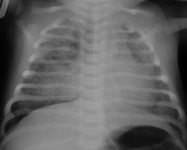

Síndrome da aspiração meconial

Do acervo de Ponthenkandath Sasidharan, MD; usado com permissão